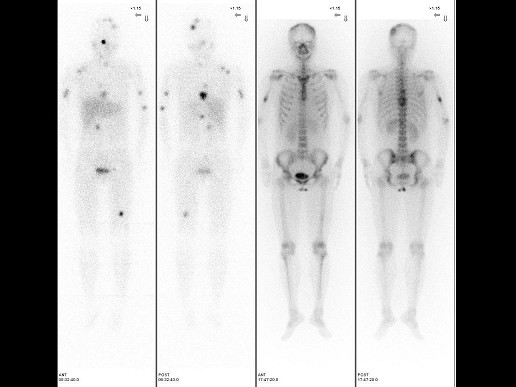

男,21岁,临床诊断胃癌,诉全身多处骨关节疼痛,行全身骨显像如图,对此影像下列描述正确的是 ( )

多选题 12-10 做题人次:1160